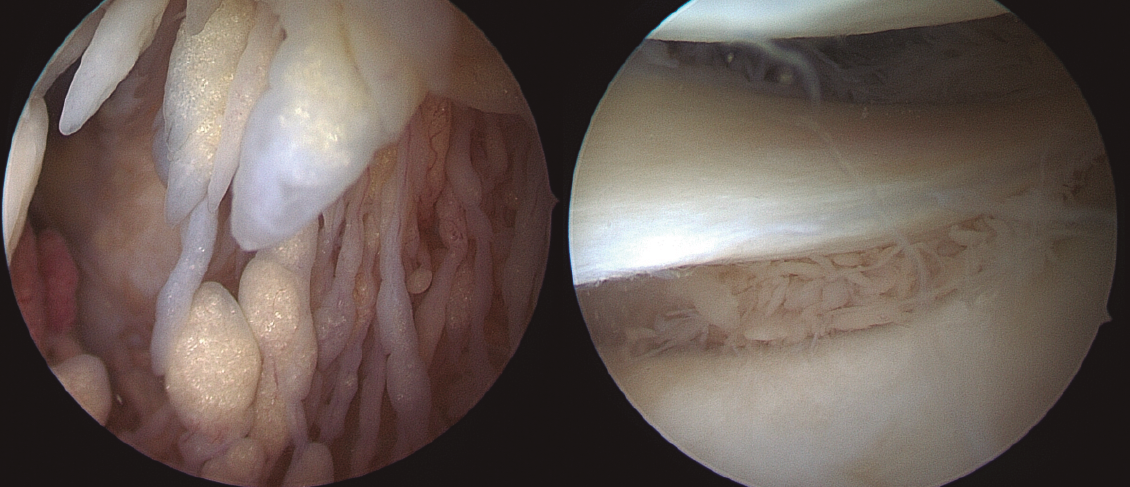

Todos los casos de hombro fueron tratados de manera artroscópica, y los hallazgos incluyeron la presencia de vellosidades características del LA (Figura 3), así como roturas en el seno del manguito rotador. Esta sinovitis proliferativa de aspecto graso se ubicaba predominantemente en la zona del intervalo rotador y en la periferia de la glena e inserción del tendón de la porción larga del bíceps.

Figura 3. Imágenes artroscópicas de las vellosidades del LA en el hombro, así como los cambios artrósicos en la articulación glenohumeral.

En los casos de la rodilla, con una intervención abierta (en el contexto de la colocación de una prótesis total de rodilla) y otra artroscópica, su localización fue predominantemente suprapatelar, si bien también se encontraron vellosidades (Figura 4).

Figura 4. Imágenes artroscópicas del LA en la rodilla, con presencia de vellosidades grasas en el receso suprapatelar e incluso en la zona supra- e inframeniscal.